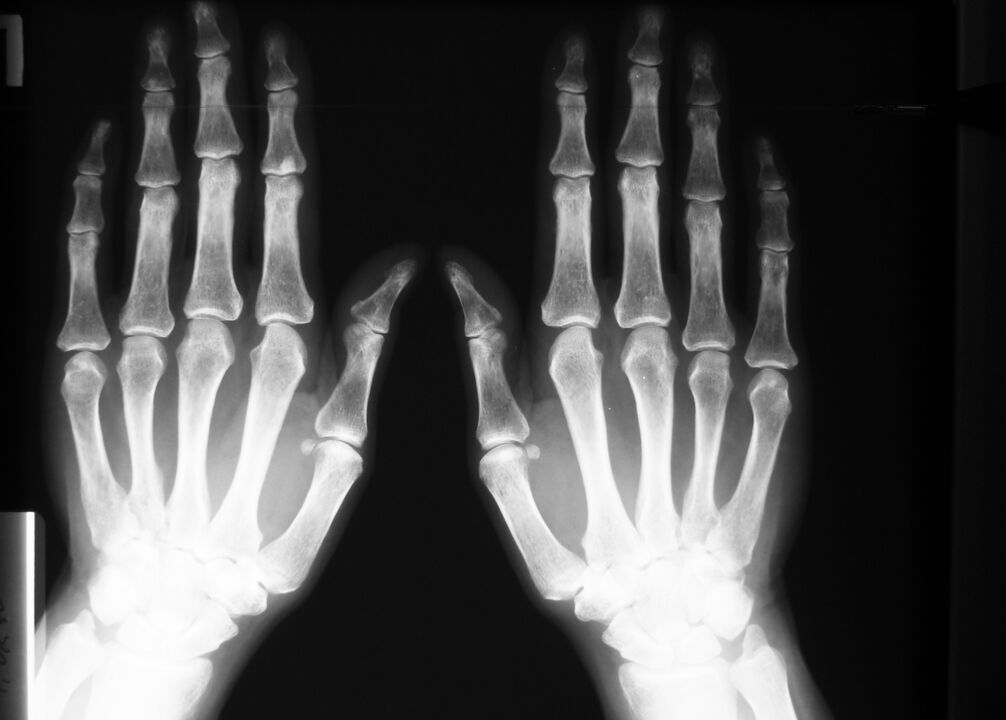

Bei degenerativen Erkrankungen und Verletzungen – Veränderungen an Gelenken: Knochengewebe und Knorpel, die auf Röntgenbildern oder Computertomographieergebnissen sichtbar sind.

Auch bei Sehnenentzündungen, Bänder- oder Muskelrissen liefert die MRT ein vollständiges Bild der Weichteilveränderungen.